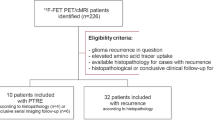

From our database, we retrospectively identified all [18F]FET-PET brain scans (n = 411) performed between January 2016 and July 2021 at Neuromed Campus, Kepler University Hospital Linz, Austria. Further selection was based on the criteria and patients’ digital records stated below. We conducted this study according to ethical principles of the Declaration of Helsinki.

Out of all patients, 37 met the inclusion criteria. We repot a median age of 55 years (range 29–84 years), 51% were female and 49% were male. Of the patients 31 (83.8%) had high grade (WHO grade III or IV) and 6 patients had low-grade (WHO grade II) glioma. Glioblastoma accounted for the highest share of all tumor subtypes (64.9%). In 9 out of 37 patients, MGMT methylation was not identified due to poor quality of the resected tissue. In the remaining 28 patients, the promotor was methylated in 17 (60.7%) and unmethylated in 11 patients (39.3%). RN was found in 6 of 17 patients (35.3%) with a methylated MGMT promotor and in 1 of 10 patients (9.1%) with an unmethylated promotor. With respect to the MGMT promotor status, further statistical analysis was not possible due to small subgroups which would have compromised the validity of the results. While all patients received at least one course of radiotherapy prior to initial scanning, 18.9% received at least a second course. The chemotherapy regimen included temozolomide in 97% and bevacizumab in 40.5% of all patients and 13.5% of all patients received at least a second tumor resection prior to initial scanning. The average interval between initial [18F]FET PET and MRI scan was 5 days. The mean follow-up (based on MRI and clinical assessment) duration was 14 months. Histopathology defined the final diagnosis (PD, n = 27; RN, n = 10) in 8 cases and radioclinical follow-up in 29. Table 1 summarizes tumor-related characteristics.